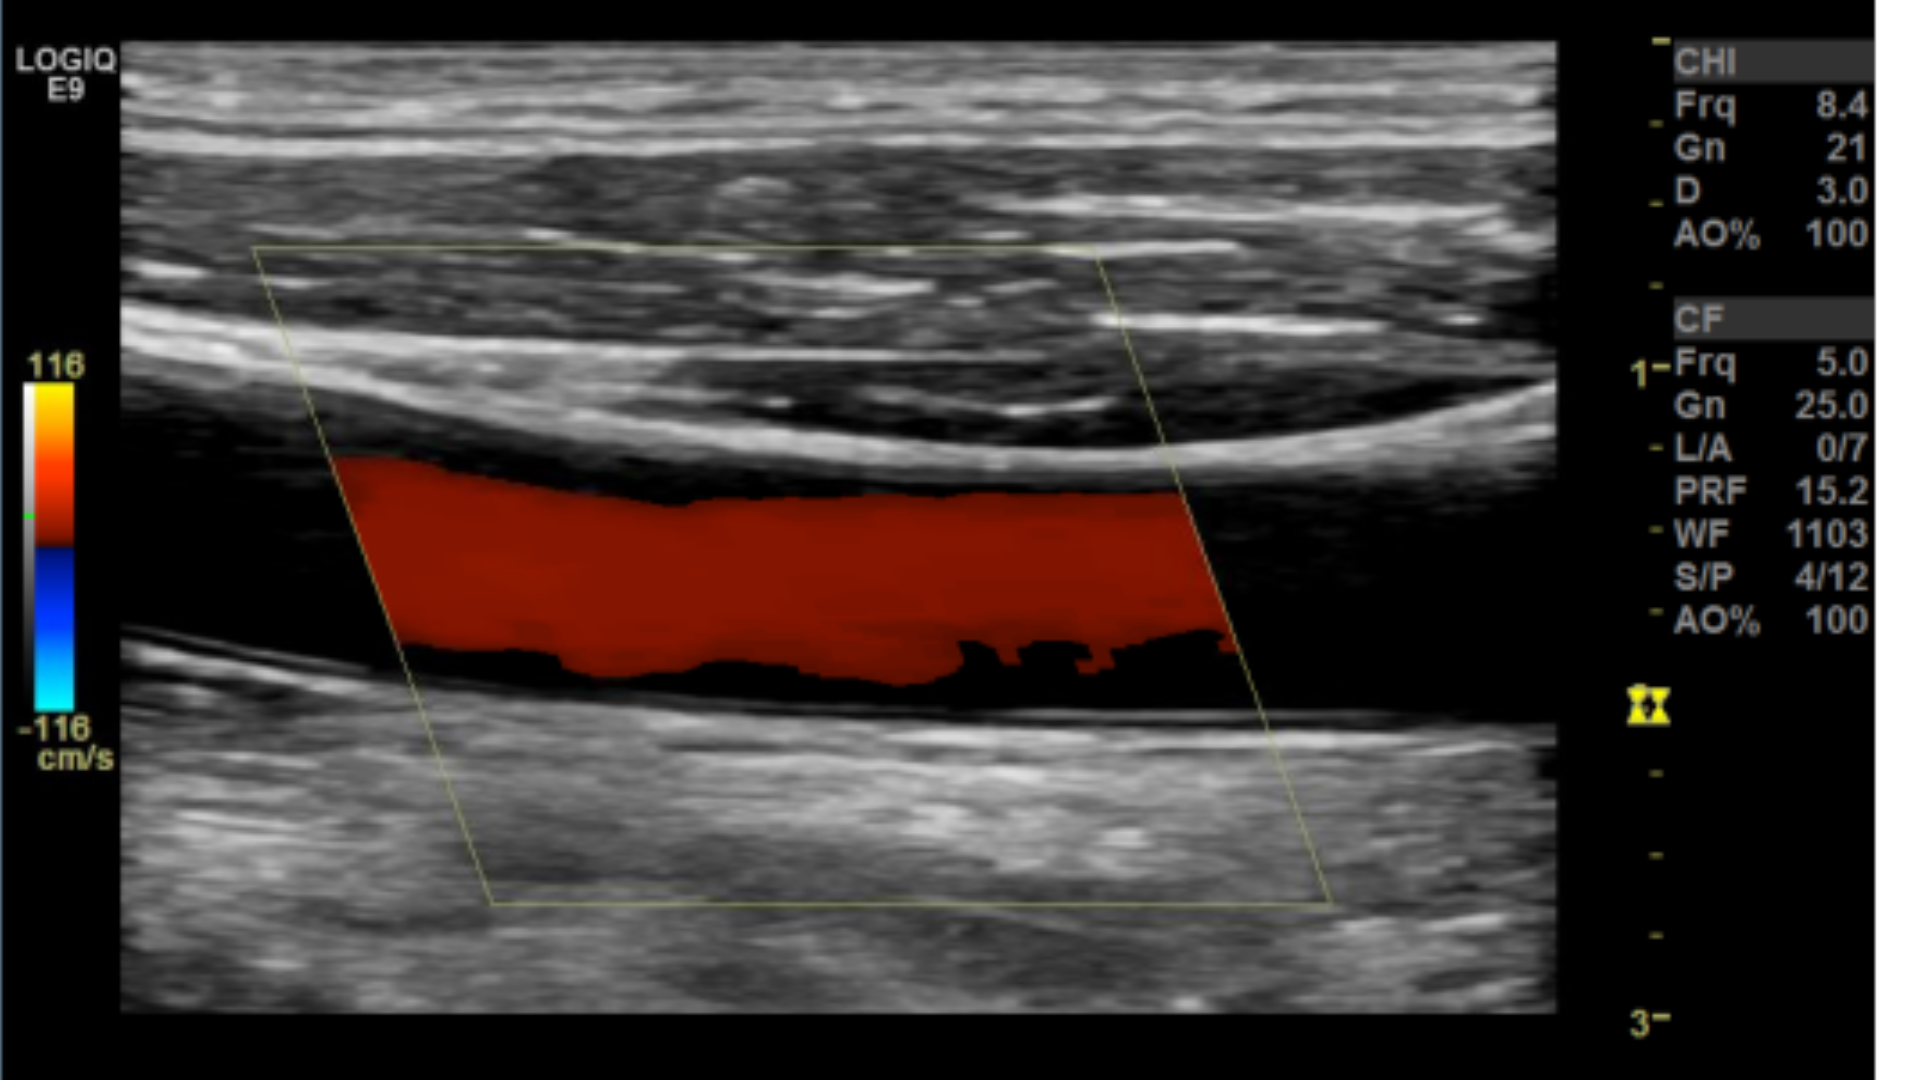

Taking technically superior images not only looks aesthetically pleasing, it is important in that it provides accurate data to render a correct diagnosis. A few parameters you may want to tweak are the doppler scale or pulse repetition frequency PRF and gain for both color and spectral doppler.

Too low of a scale and you’ll get aliasing which makes getting a proper velocity impossible.

Scale/PRF too low